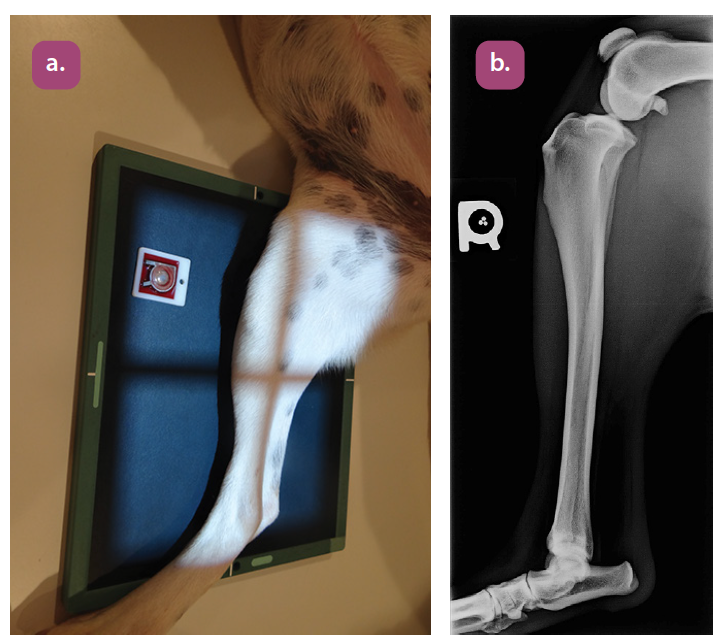

mediolateral projection of the tibia

caudocranial projection of the tibia and fibula